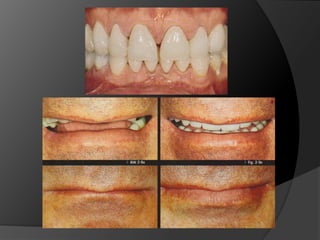

Planificación del TratamientoEl éxito de los tratamientos de rehabilitación está directamente asociado a una planificación correcta y con criterio, que debe ser individualizada y ejecutada con el objeto de atender las necesidades de cada pacientePrótesis Fija. Luiz Fernando Pegoraro

Planificación del TratamientoEléxito de los tratamientos de rehabilitación está directamente asociado a una planificación correcta y con criterio, que debe ser individualizada y ejecutada con el objeto de atender las necesidades de cada pacientePrótesis Fija. Luiz Fernando Pegoraro